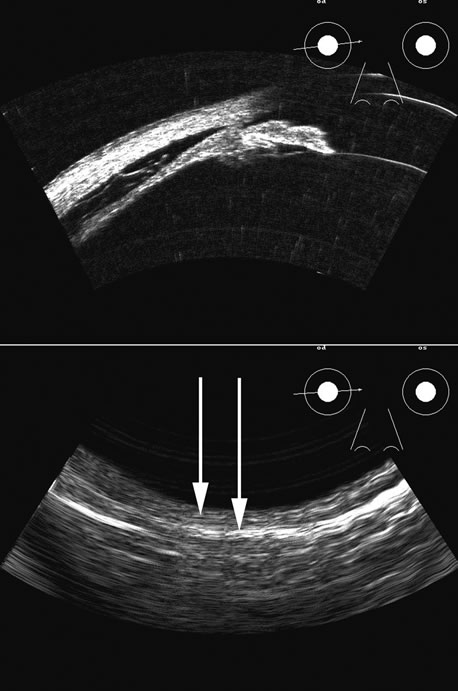

Hypotony is easily diagnosed by direct measurement of intraocular pressure, but the underlying cause is difficult to evaluate.11 High-frequency ultrasound scans can easily reveal separation of the ciliary body and the sclera. This allows different forms of hypotony to be determined—for example: tractional with membrane attached; primary as idiopathic, often inflammatory or hemorrhagic; and dehiscence secondary to iridodialysis or scleral perforation (Fig. 6).

Fig. 6. Hypotony of the eye generally is easily diagnosed by a separation of the ciliary body from the sclera. We have noted several types of such separation, such as tractional, primary (idiopathic), and dehiscence secondary to iridodialysis or scleral perforation, as in filtration procedures. In our series, greater than two clock hours of separation is typical of hypotony. The lower figure shows a concomitant thickening of the retina-choroid complex, also seen in hypotony (arrows). Long-standing hypotony typically has a shortened globe and possible retinal or choroidal separation.